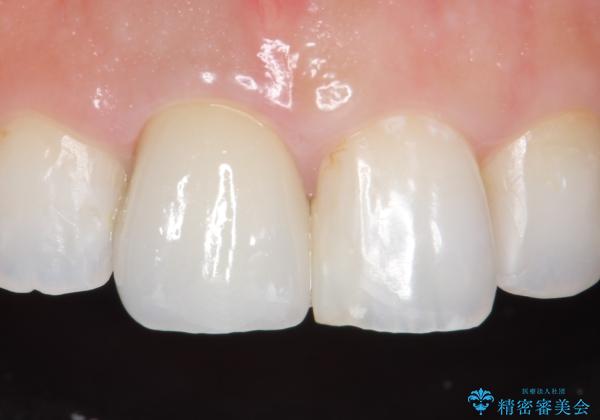

- 右上1の前歯の見た目が気になるので被せ物をやり替えたいといらっしゃった方の症例です。

再根管治療終了後、オールセラミッククラウン(スペシャル)によって隣在歯に合わせた補綴を行いました。

前歯の補綴ではオールセラミッククラウンを希望される患者様が多いですが、オールセラミッククラウンの中でも、エコノミー、スタンダード、スペシャル、エクセレントとランクがあります。

その中でも特に審美性が高いのがスペシャル、エクセレントです。スペシャル、エクセレントは口腔内写真をもとに熟練の技工士が、患者様の口腔内に合わせたオーダーメイドのクラウンを製作致します。